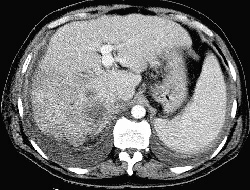

RADIOLOGY: HEPATOBILIARY: Case# 32870: CIRRHOSIS, GALLBLADDER VARICES, HEPATOCELLULAR CARCINOMA. 59 year old white male for evaluation of hepatic mass/pseudocyst diagnosed two weeks ago. Patients alpha-fetoprotein is markedly elevated. The liver has cirrhotic morphology along with ill- defined heterogeneous infiltrating mass involving the right hepatic lobe and extending into the caudate lobe inferiorly. There are large areas of necrosis in it. The mass compressing approximately 5 cm of lower intrahepatic IVC. Direct IVC invasion cannot be certainly excluded. Multiple varices are seen involving the splenic hilum, gastrosplenic, gastrohepatic ligament, gastric wall, paraumbilical as well as gallbladder wall. A small amount of ascites is present. There is splenic enlargement without focal lesions. Liver cirrhosis is characterized by a generalized disorganization of hepatic archictecture with scarring and nodule formation. Other sequelae include liver cell damage, regenerative activity, and generalized fibrosis resulting in a nodular pattern. There is an increased incidence of hepatocelluar carcinoma associated with cirrhosis of the liver. Causes of cirrhosis include prolonged alcohol intake, viral hepatitis, biliary obstruction, Wilsons disease, and heart failure with long-standing chronic passive congestion of the liver. Alcoholic (Laennecs, nutritional) cirrhosis is the most frequently occurring form of the disorder. Clinical manifestations of the disease include jaundice, hypoalbuminemia, coagulation factor deficiencies, hyperstrinism, and intrahepatic scarring with increased portal venous pressure. The increase in portal venous pressure can lead to esophageal varices, rectal hemorrhiods, periumbilical venous collaterals (caput medusae), and splenomegaly. Morphologically, the liver may be enlarged or small and shrunken depending upon the progression of the disease. The nodular pattern is most often micronodular in alcoholic cirrhosis. Hepatic architecture is obscured by fibrous bands surrounding nodules of distorted liver cell plates. The fibrous bands contain proliferating bile ducts and inflammatory cells. In the final stages of cirrhosis the nodules become larger and more irregular resulting in a scarred, shrunken liver referred to as a "hobnail liver". Patients with cirrhosis of the liver often present with the following radiological findings. Fatty infiltration with hepatomegaly can be seen in the early stages of cirrhosis. Other characteristic findings include non-uniform attenuation due to chronic fatty infiltration and irregular fibrosis, irregular lobulated hepatic contour due to areas of atrophy and nodular regeneration, intrahepatic regenerating nodules, atrophy of the right lobe and hypertrophy of the left and caudate lobes, decreased liver volume accompanying chronic cirrhosis, increased size and prominence of the intrahepatic fissure due to shrunken liver parenchyma, signs of portal hypertension, and ascites. A ratio comparing the sizes of the caudate lobe and right lobe is a good diagnostic indicator of patients with cirrhosis. The caudate is measured transversely from the medial aspect of the caudate to the lateral aspect of the main portal vein. The right lobe is measured from this same point at the portal vein to the right lateral margin of the liver. A caudate-to-right-lobe ratio greater than 0.65 provides 96% confidence in the diagnosis of cirrhosis. A caudate-to-right-lobe ratio less then 0.6 makes cirrhosis unlikely, whereas a ratio of 0.37 is the average for normal livers.